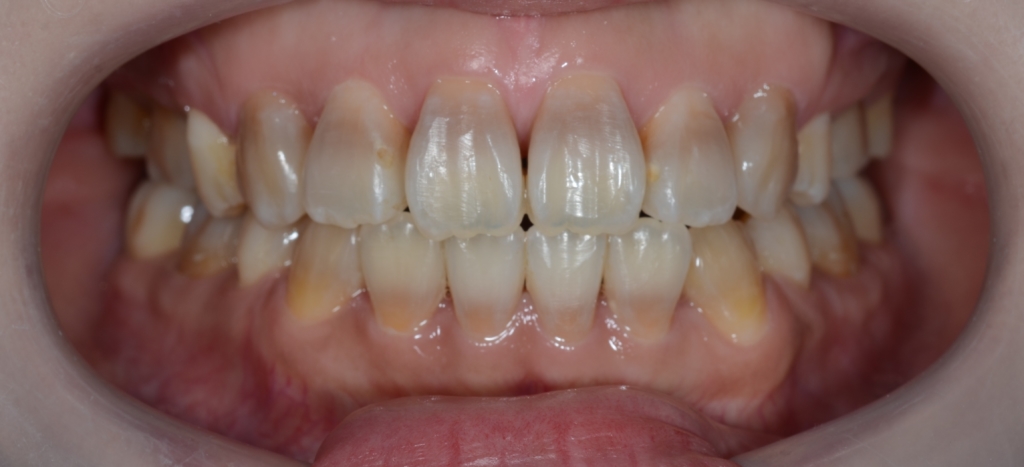

【After】

「もう十分です」という患者さんの声に許してもらいました

【保定】 上下ともフィックスタイプ&クリアリテーナー

【治療期間】 2年3カ月間

【治療費用】 81万6千円

あらためて、矯正治療前後の歯並びと口元の変化を比べてみましょう。

まずは、歯並びの変化です。

口元がスッキリして、オトガイにあった梅干し状のシワもほぼ無くなりました

今回は、歯並びをきれいにすることが一番! 口元の変化はあわよくばを狙った二番!でしたが、

歯並びはもちろん、口元もスッキリさせることが出来ました。

お口を閉じるのも、とても楽になった!と合わせて喜んでもらいました。